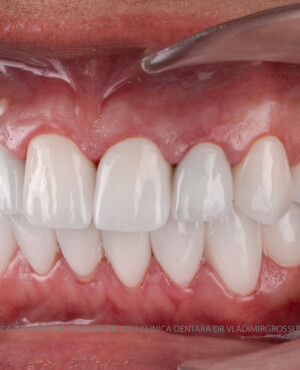

Transformările estetice și impactul reabilitării asupra vieții pacienților

Reabilitarea dentară produce o schimbare vizibilă și profundă în aspectul pacientului, cu efecte pozitive evidente asupra stimei de sine și a calității vieții. Mulți pacienți relatează bucuria redobândirii funcției masticatorii și dispariția complexelor legate de aspectul dentar.